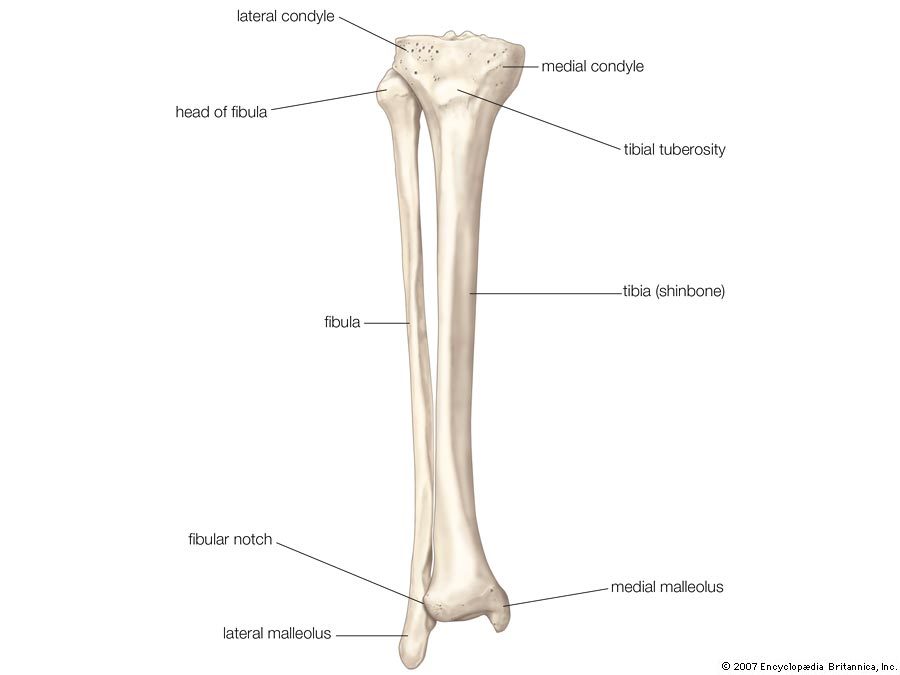

Remind yourself of the bony anatomy of the tibia

*On posterior have soleal line